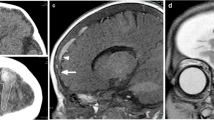

Patterns of venous and sinus abnormalities. Graphic demonstrates: a Positive lollipop sign. The bridging vein (short arrow) terminates in a subarachnoid blood clot (long arrow) and does not drain into the sinus. b Lack of lollipop sign. The bridging vein (short arrow) goes through the blood clot (long arrow) and subdural hemorrhage and drains into the sinus. c Positive compression sign. The bridging vein (short arrow) terminates abruptly without any associated blood clot at its termination

Lollipop sign in a 31-month-old boy who presented with tibial metaphyseal fracture, multiple vertebral compression fractures, bilateral subdural hemorrhage, retinal hemorrhage and diffuse hypoxic–ischemic injury of the brain. Brain MRI demonstrates lollipop sign (arrows) overlying the left cerebral convexity, which is (a) hypointense with blooming on axial T2* gradient recalled echo sequence. b, c CT venogram confirms terminal hyperattenuation on (b) unenhanced image and lack of intraluminal contrast on (c) post-contrast CT in the cortical bridging vein in question, which terminates abruptly

Cortical bridging vein in a 7-month-old boy. a Coronal MP-RAGE MR sequence demonstrates large mixed-signal-intensity subdural hematoma bilaterally with cortical bridging vein extending through the subdural hematoma and draining into the superior sagittal sinus on the left side (arrow). b Three-dimensional phase-contrast MR venography demonstrates the cortical bridging vein draining into the superior sagittal sinus. There is mild stenosis of the vein where it crosses the dura (arrow). Displacement of the cortical vein is also well demonstrated on the left side (arrowheads). MP-RAGE magnetization-prepared rapid gradient echo imaging

Compression sign in a 5-month-old girl with multiple rib and extremity fractures, retinal hemorrhage, cervical spine ligamentous injuries and spinal subdural hematoma. a Coronal MP-RAGE MR sequence of the brain demonstrates left-side subdural hematoma hypointense to gray matter overlying the convexity (arrow). b Three-dimensional phase-contrast MR venography shows paucity and abrupt termination of cortical bridging veins draining into the superior sagittal sinus superiorly on the left side (arrow), consistent with absent flow distally resulting from positive compression sign. No evidence of lollipop sign or intraluminal thrombosis was seen on other sequences. It is important to not mistake this appearance of paucity of cortical veins on MR venography as widespread thrombosis. MP-RAGE magnetization-prepared rapid gradient echo imaging

Lollipop and compression signs in a 2-month-old boy with multiple extremity and rib fractures. a Coronal MP-RAGE MR sequence demonstrates large subdural hemorrhage bilaterally (arrows). b Axial T2* gradient recalled echo sequence shows lollipop sign with a torn bridging vein terminating in a clot with terminal thrombosis, demonstrating blooming (arrow) with bilateral subdural hemorrhage (arrowheads). c Reconstructed MR venography sequence demonstrates paucity of cortical bridging veins draining into the superior sagittal sinus superiorly, consistent with compression. MP-RAGE magnetization-prepared rapid gradient echo imaging